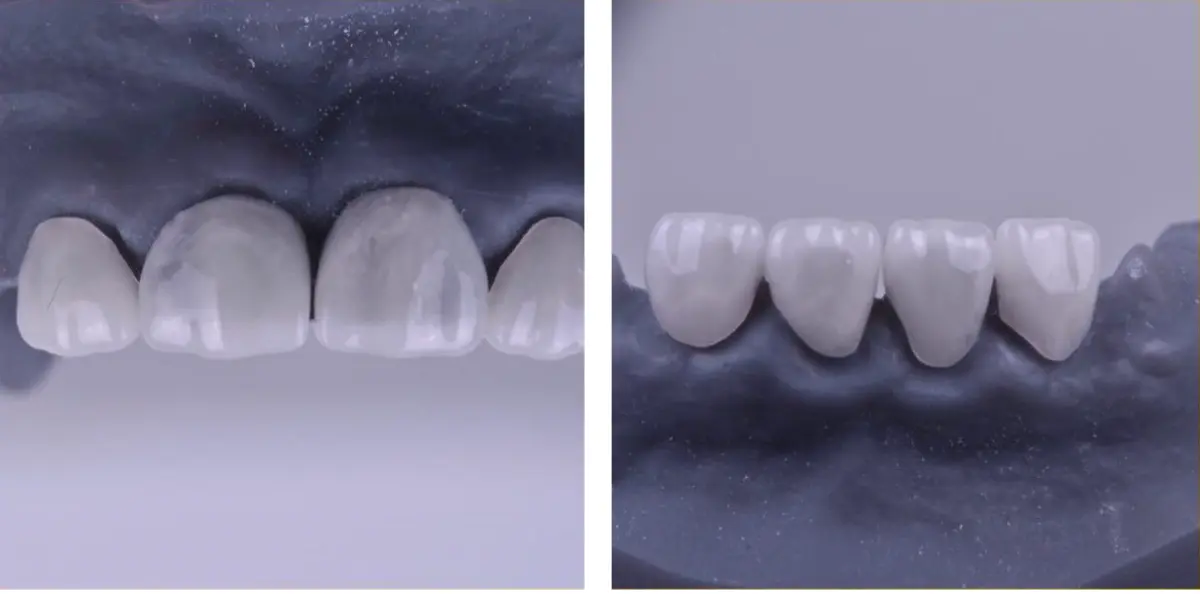

Детские зубные коронки

Значительное разрушение зубов у детей давно не приговор – восстановление возможно при помощи коронок. Часто этот способ лечения ассоциируется со взрослой стоматологией, но на самом деле детские зубные коронки появились в 50-х годах прошлого века и сейчас активно используются в зарубежной практике.